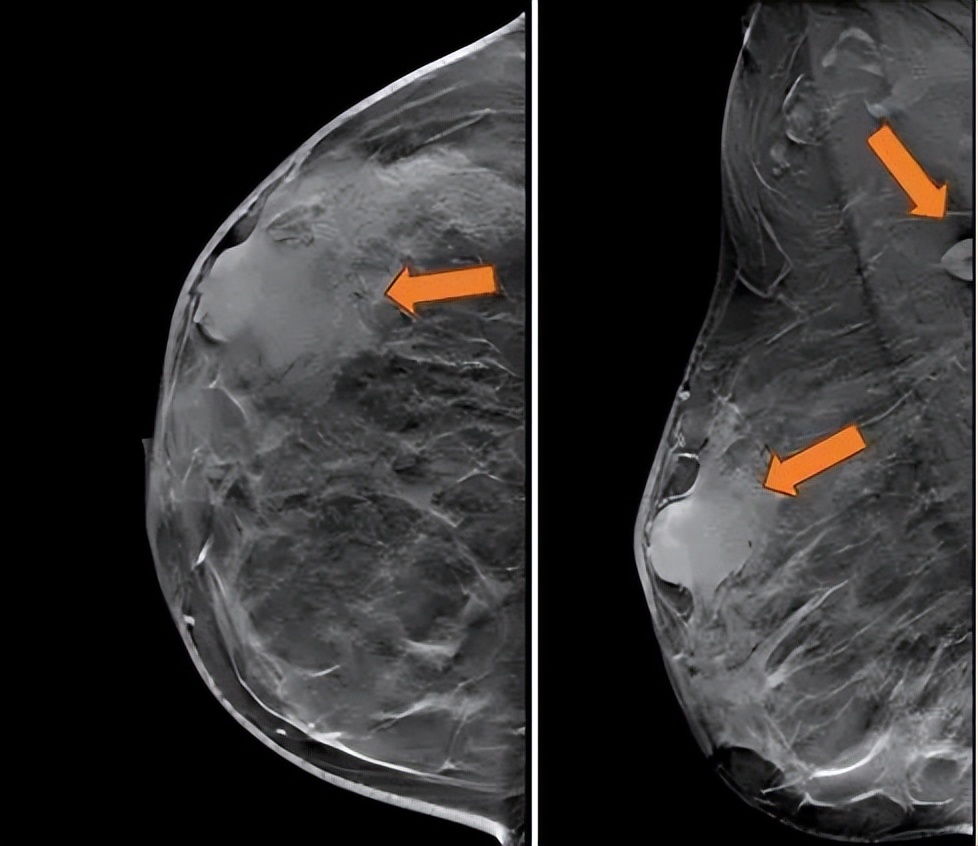

2021.7.6 钼靶示: 右乳外上象限肿块,考虑乳腺癌(BI-RADS-5类)右腋下肿大淋巴结,M灶可能。

右乳外上象限不规则高密度肿块,边缘毛糙,大小约3.3×2.7cm,邻近皮肤牵拉增厚,右腋下见肿大淋巴结。

图2. 钼靶

(3 cycle 后)2021.9.21 钼靶示:右乳外上象限不规则形肿块明显缩小,右腋窝淋巴结亦较前缩小。

图6. 钼靶